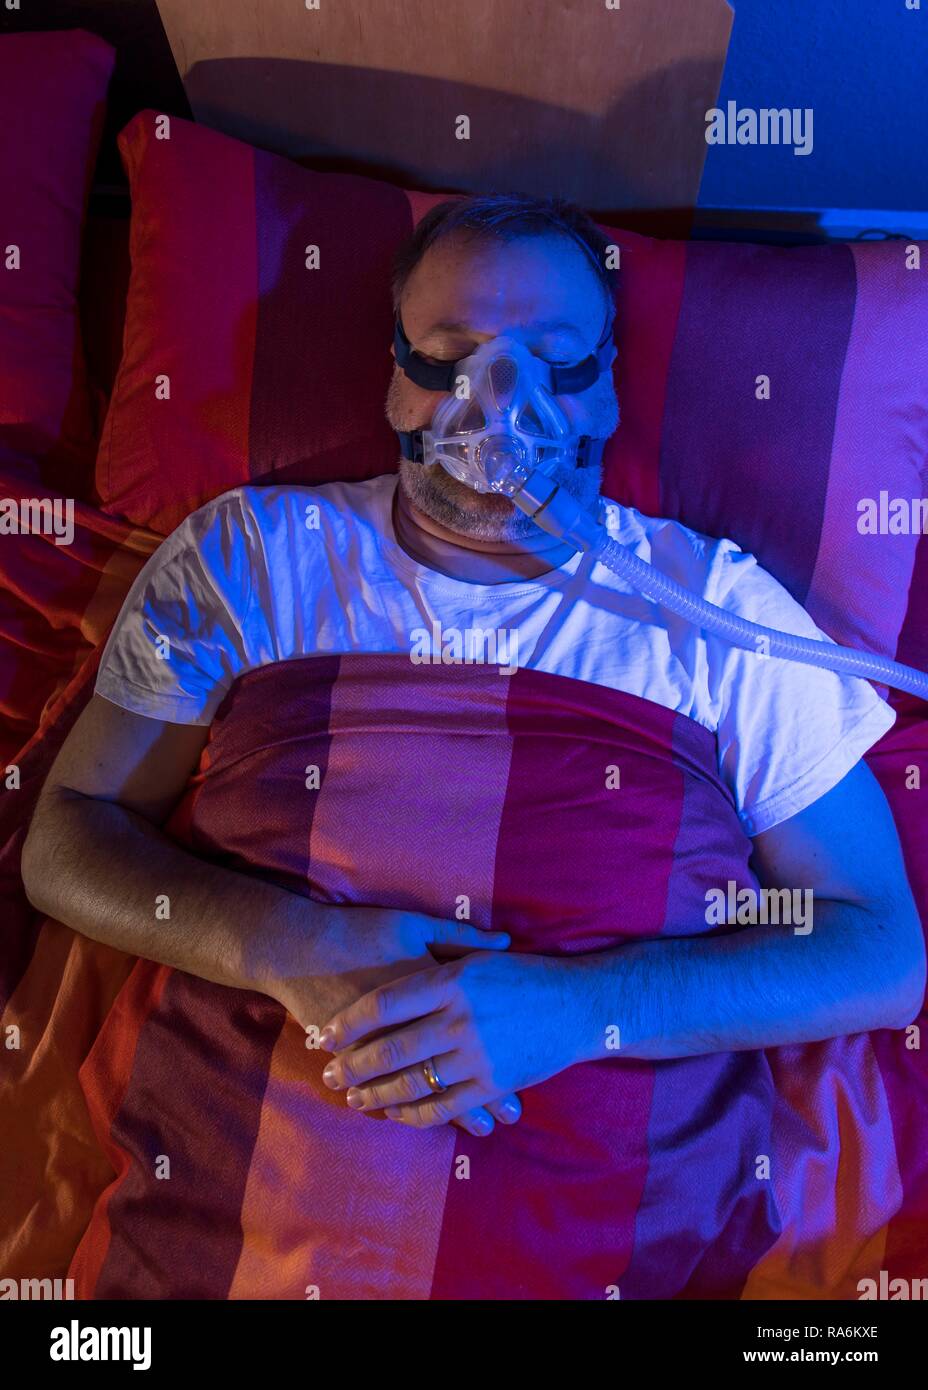

Man with sleep apnea syndrome, wears a CPAP mask while sleeping, breathing mask, which pushes air into the respiratory tract due Stock Photohttps://www.alamy.com/image-license-details/?v=1https://www.alamy.com/man-with-sleep-apnea-syndrome-wears-a-cpap-mask-while-sleeping-breathing-mask-which-pushes-air-into-the-respiratory-tract-due-image230028697.html

Man with sleep apnea syndrome, wears a CPAP mask while sleeping, breathing mask, which pushes air into the respiratory tract due Stock Photohttps://www.alamy.com/image-license-details/?v=1https://www.alamy.com/man-with-sleep-apnea-syndrome-wears-a-cpap-mask-while-sleeping-breathing-mask-which-pushes-air-into-the-respiratory-tract-due-image230028697.htmlRMRA6KXH–Man with sleep apnea syndrome, wears a CPAP mask while sleeping, breathing mask, which pushes air into the respiratory tract due

Man with sleep apnea syndrome, wears a CPAP mask while sleeping, breathing mask, which pushes air into the respiratory tract due Stock Photohttps://www.alamy.com/image-license-details/?v=1https://www.alamy.com/man-with-sleep-apnea-syndrome-wears-a-cpap-mask-while-sleeping-breathing-mask-which-pushes-air-into-the-respiratory-tract-due-image230028658.html

Man with sleep apnea syndrome, wears a CPAP mask while sleeping, breathing mask, which pushes air into the respiratory tract due Stock Photohttps://www.alamy.com/image-license-details/?v=1https://www.alamy.com/man-with-sleep-apnea-syndrome-wears-a-cpap-mask-while-sleeping-breathing-mask-which-pushes-air-into-the-respiratory-tract-due-image230028658.htmlRMRA6KW6–Man with sleep apnea syndrome, wears a CPAP mask while sleeping, breathing mask, which pushes air into the respiratory tract due

Man with sleep apnea syndrome, wears a CPAP mask while sleeping, breathing mask, which pushes air into the respiratory tract due Stock Photohttps://www.alamy.com/image-license-details/?v=1https://www.alamy.com/man-with-sleep-apnea-syndrome-wears-a-cpap-mask-while-sleeping-breathing-mask-which-pushes-air-into-the-respiratory-tract-due-image230028691.html

Man with sleep apnea syndrome, wears a CPAP mask while sleeping, breathing mask, which pushes air into the respiratory tract due Stock Photohttps://www.alamy.com/image-license-details/?v=1https://www.alamy.com/man-with-sleep-apnea-syndrome-wears-a-cpap-mask-while-sleeping-breathing-mask-which-pushes-air-into-the-respiratory-tract-due-image230028691.htmlRMRA6KXB–Man with sleep apnea syndrome, wears a CPAP mask while sleeping, breathing mask, which pushes air into the respiratory tract due

Man with sleep apnea syndrome, wears a CPAP mask while sleeping, breathing mask, which pushes air into the respiratory tract due Stock Photohttps://www.alamy.com/image-license-details/?v=1https://www.alamy.com/man-with-sleep-apnea-syndrome-wears-a-cpap-mask-while-sleeping-breathing-mask-which-pushes-air-into-the-respiratory-tract-due-image230028694.html

Man with sleep apnea syndrome, wears a CPAP mask while sleeping, breathing mask, which pushes air into the respiratory tract due Stock Photohttps://www.alamy.com/image-license-details/?v=1https://www.alamy.com/man-with-sleep-apnea-syndrome-wears-a-cpap-mask-while-sleeping-breathing-mask-which-pushes-air-into-the-respiratory-tract-due-image230028694.htmlRMRA6KXE–Man with sleep apnea syndrome, wears a CPAP mask while sleeping, breathing mask, which pushes air into the respiratory tract due